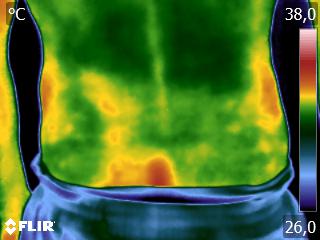

Como na sequência de termogramas abaixo de um paciente do sexo masculino, de 44 anos, sem comorbidades e praticante de atividade física que apresentou fortes dores em braço esquerdo (com irradiação para antebraço) após treino de musculação. Esta dor chegou a ser incapacitante, pois impossibilitava inclusive o paciente a realizar atividades de vida diárias como pegar um copo de água.

Após a realização de uma Análise Termofuncional©®, foi detectado alterações térmicas em “linha”, margeando as fibras musculares e tendíneas inferiores (insercionais) bicipitais. Estas alterações também aventaram a hipótese de dilatação venosa, por alguma reação inflamatória local. Foi realizado então aplicação de laserterapia através da Técnica Termoguiada, que acabou por promover a completa analgesia em 24 horas após aplicação.